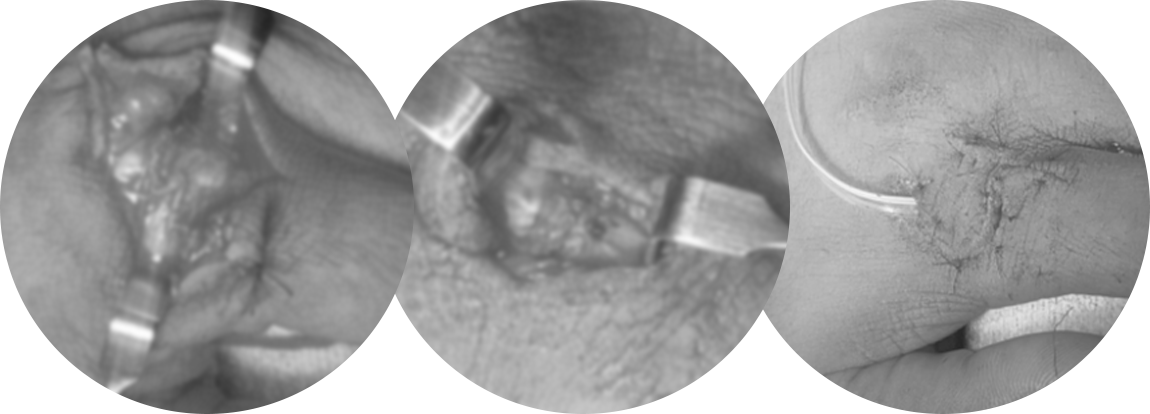

건 봉합

손가락 끝 작은 신경, 혈관 봉합

독일 Carl Zeiss 사에서 제조한 미세현미경을 이용하여 미세혈관 같이 육안으로 식별이 어려운 부위를 20배 이상 확대하여 미세한 환부의 수술을 가능하게 합니다.